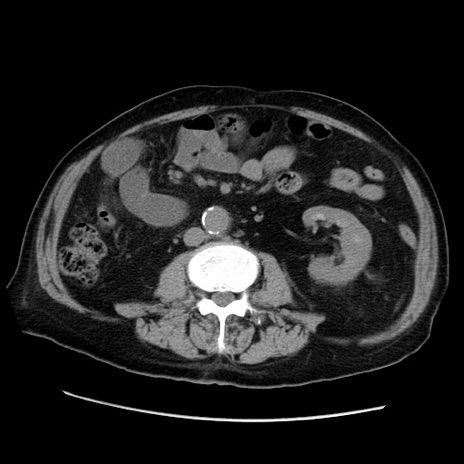

症例21(横断像)

【症例】70歳代男性

【主訴】腹痛

【現病歴】肝硬変・肝細胞癌にてかかりつけの方。約9時間前に食後より腹痛出現。症状が徐々に増悪し、嘔吐出現したため来院。

【既往歴】肝硬変、肝細胞癌(RFA、TACE後)

【身体所見】意識清明、表情苦悶様、BT 36℃、BP 129/78mmHg、P 88bpm、SpO2 97%(RA)、右上腹部から心窩部にかけて圧痛あり、反跳痛なし、筋性防御あり。

【データ】WBC 5800、CRP 0.16